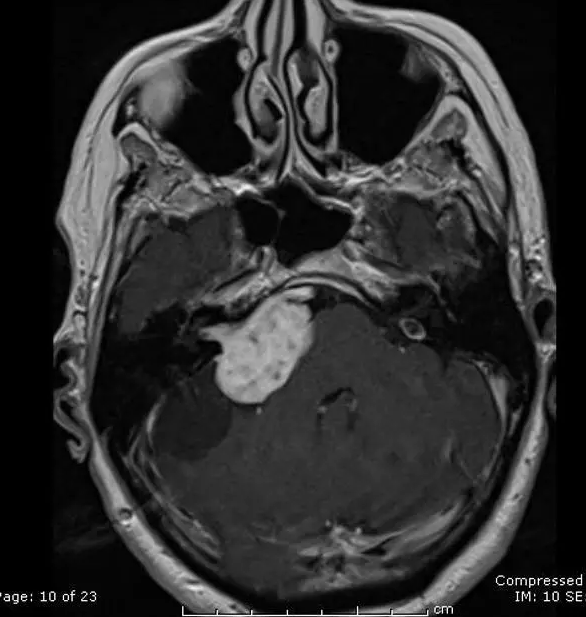

INC国际神经外科顾问团成员、国际神经外科学院前主席、加拿大多伦多儿童医院神经外科主任James T.Rutka教授表示,小脑占位就是平时的小脑肿瘤,不全是恶性的,看什么年龄和什么位置。小孩子可能常见的是室管膜瘤,是低度恶性;髓母细胞瘤是高度恶性的。还有一种相对比较好的毛细胞新型细胞瘤,这个是一级的,相对预后是比较好的。老年人可能转移瘤、恶性肿瘤多见。但也有一些小脑脑膜瘤,一般是良性的。如果通过正确的治疗方案,是可能治好的,其生存时间、生存力也长的。

James T.Rutka教授表示,小脑作为大脑的重要组成部分,其功能不仅繁杂,而且都很重要,一句话总结就是承担运动控制中预期性的前馈控制和基于误差的监督学习这两种功能。其位于大脑的后下方、颅后窝内、延髓和脑桥的背面。脑瘤部位在小脑就说明比较深,对于小脑占位的肿瘤应该优选手术治疗,在高手术切除率下,患者将有一个更好的预后,如果手术未切除干净,术后可以采用放射治疗以消灭残余肿瘤。如果部位不允许手术,还可以放疗、化疗、靶向治疗等来治疗。